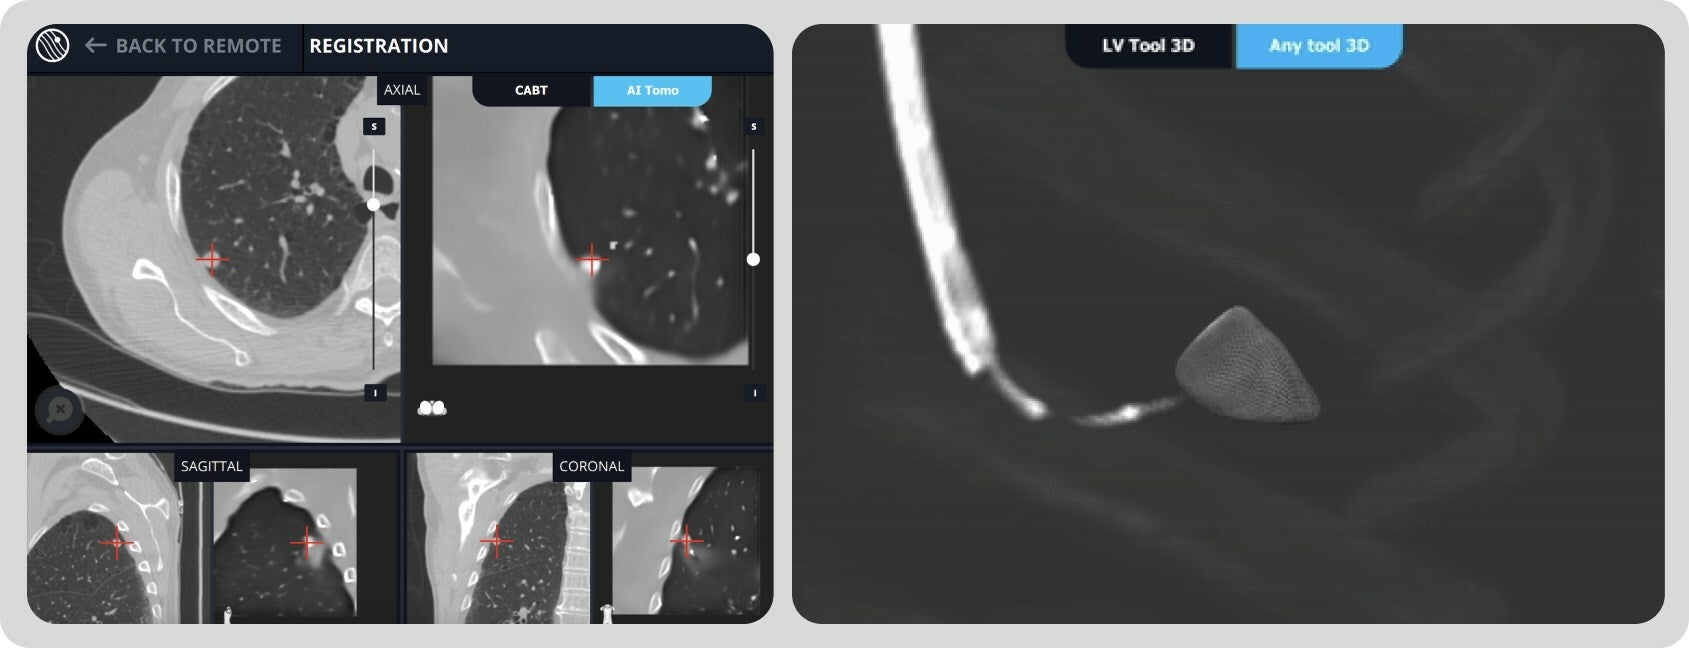

Making significant improvements to its AI-driven imaging algorithms, Body Vision’s latest software release supports the improved navigational accuracy and diagnostic success that clinicians strive for by providing key improvements in the real-time image quality achievable with LungVision™ AI Tomography during a lung nodule biopsy procedure.

The latest software also streamlines the LungVision™ workflow when used in conjunction with robotic bronchoscopy platforms like the Ethicon Monarch and Ion by Intuitive Surgical by eliminating the need for C-arm spins during registration. In addition to substantially  shortening the time required to complete a lung nodule biopsy procedure with real-time imaging, the abridged workflow also reduces radiation exposure to medical staff and the patient. With the latest update, when using a standard 2D C-arm, radiation exposure is potentially one-third that of the previous LungVision™ workflow which was shown to already be roughly one-fifth of the dose per spin of a 3D-capable C-arm.

LungVision™ harnesses the power of artificial intelligence (AI) to seamlessly transform X-ray images acquired from any C-arm into real-time intraoperative CT scans. This revolutionary  technology empowers bronchoscopists with the ability to visualize pulmonary lesions in real-time during diagnostic bronchoscopy. By significantly augmenting the accuracy and precision of lung nodule biopsies through image-guidance, LungVision™ has the potential to enable earlier-stage cancer detection and improve lung cancer survival rates.